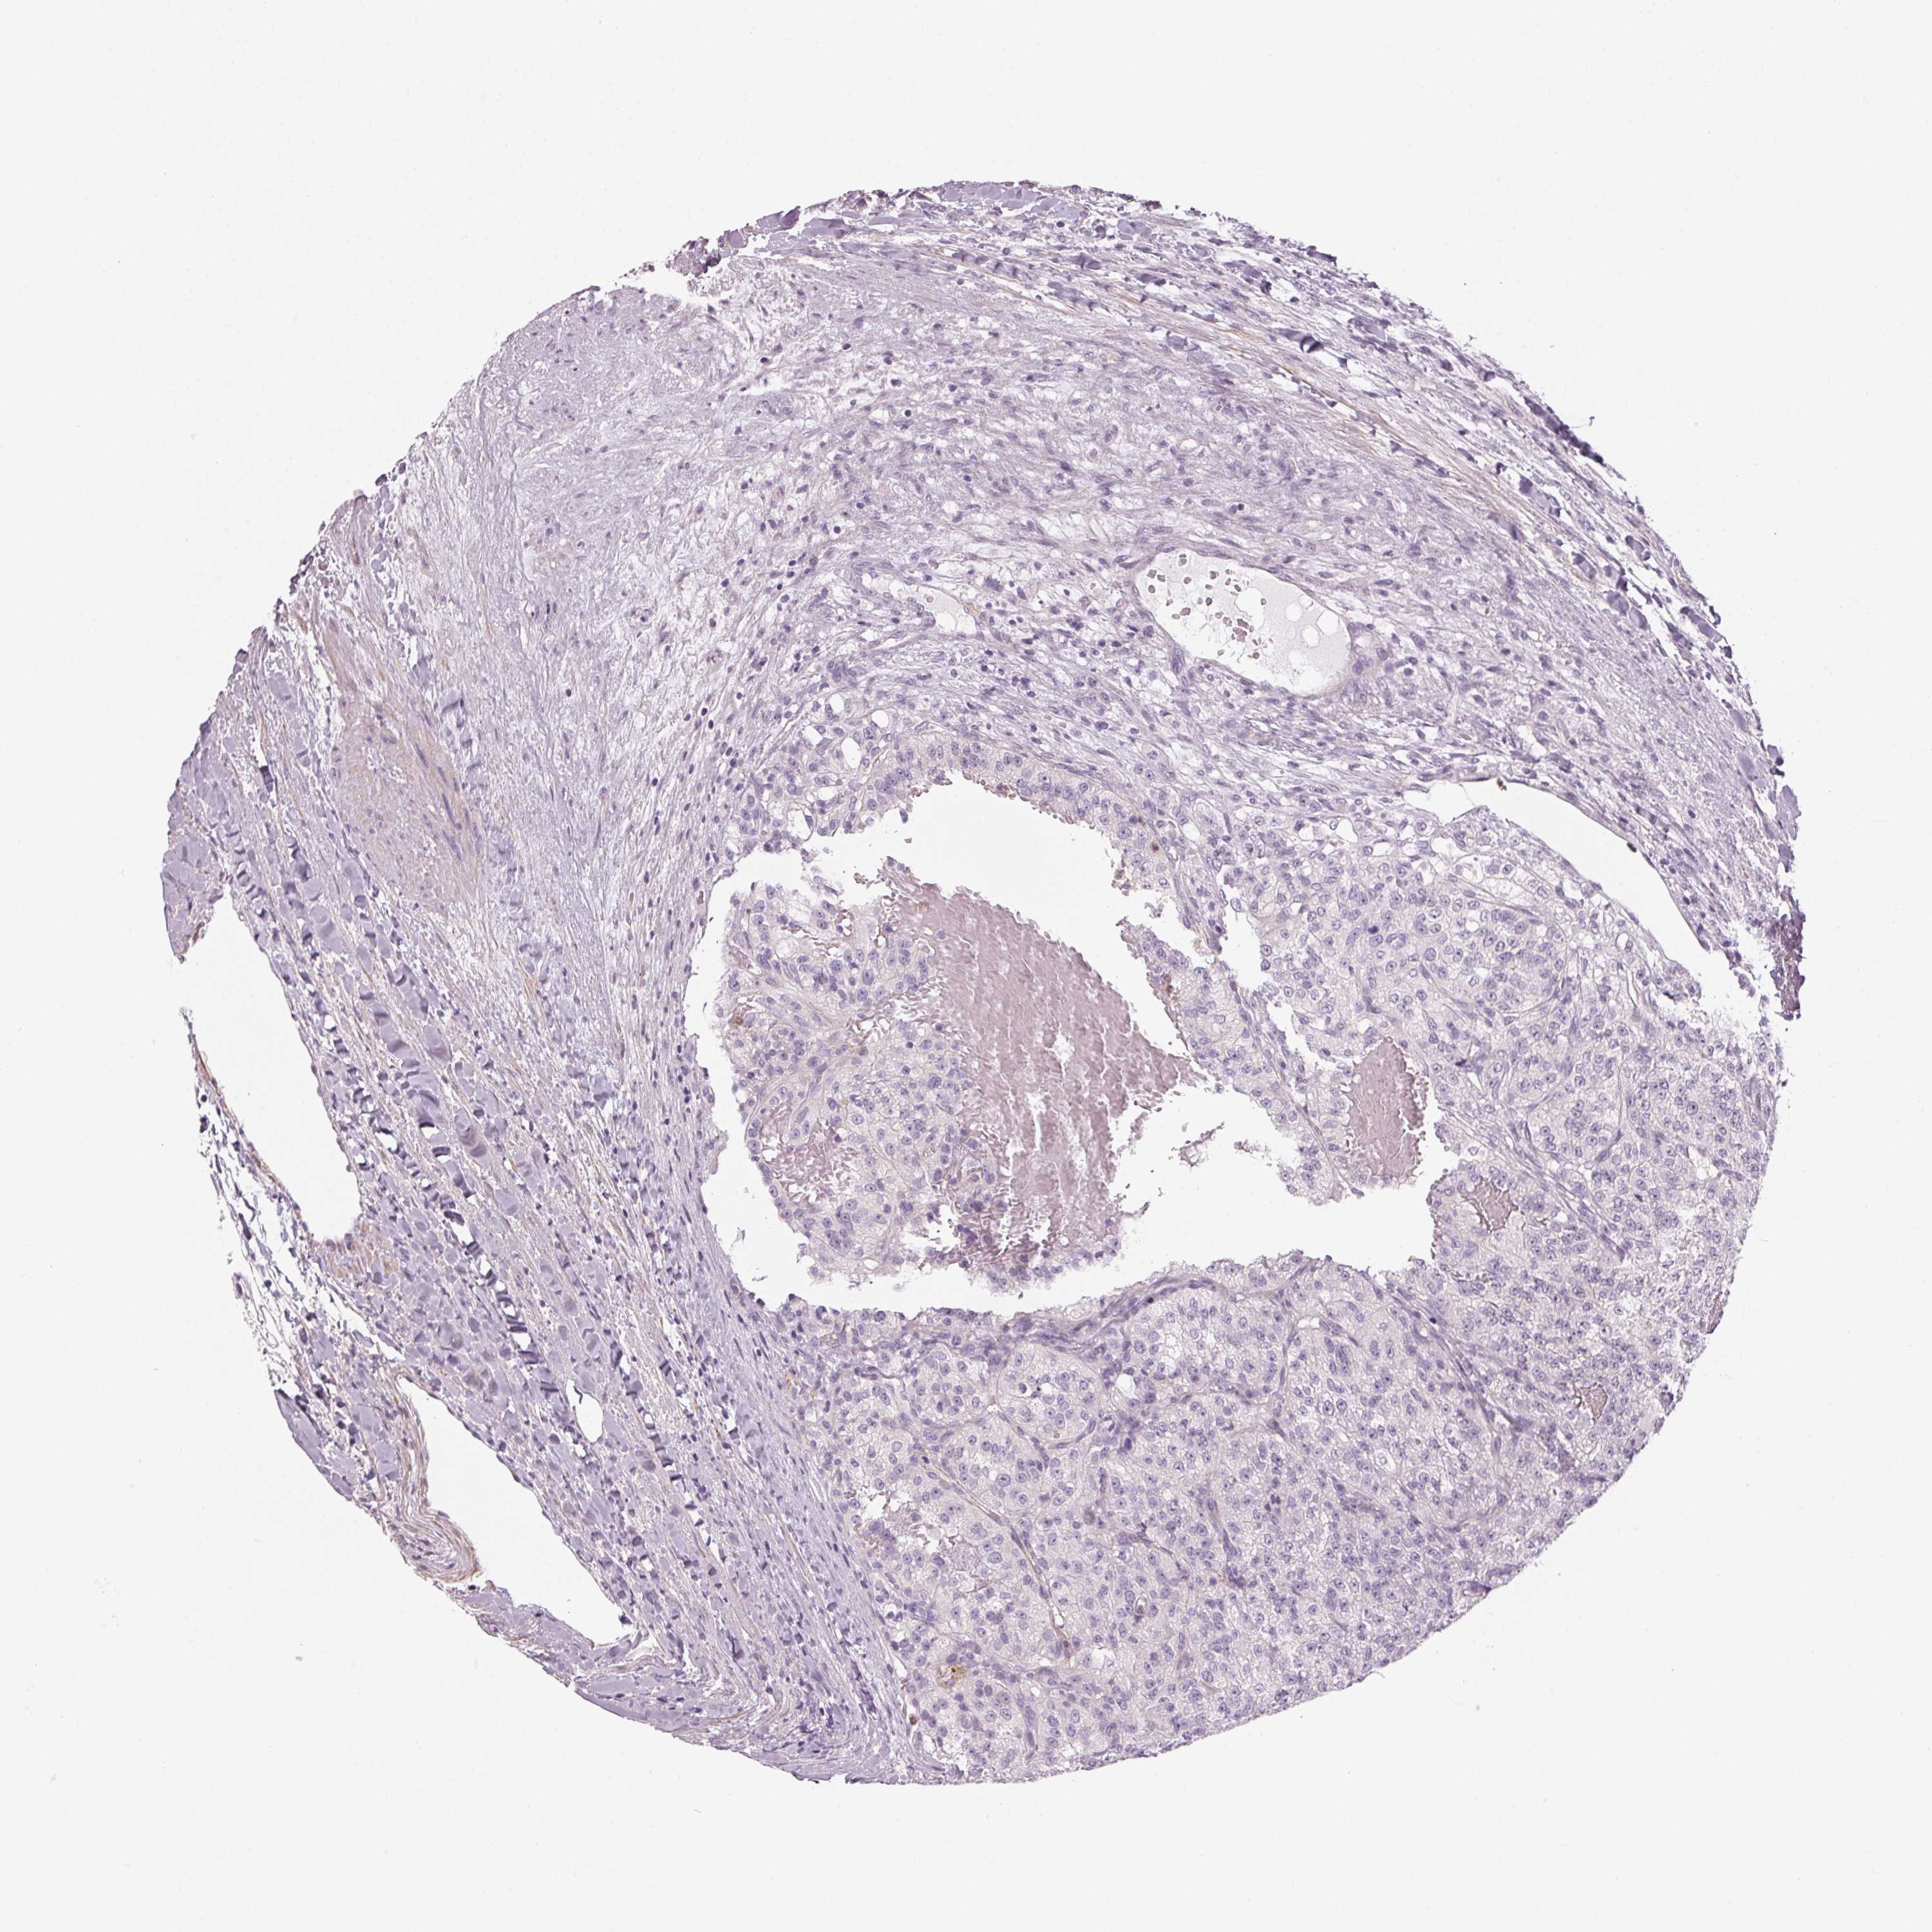

KIDNEY RENAL CLEAR CELL CARCINOMA (VALIDATION) - Interactive survival scatter ploti

The Survival Scatter plot shows the clinical status (i.e. dead or alive) for all individuals in the patient cohort, based on the same data that underlies the corresponding Kaplan-Meier plots. Patients that are alive at last time for follow-up are shown in blue and patients who have died during the study are shown in red.

The x-axis shows the expression levels (FPKM) of the investigated gene in the tumor tissue at the time of diagnosis. The y-axis shows the follow-up time after diagnosis (years). Both axes are complimented with kernel density curves demonstrating the data density over the axes. The top density plot shows the expression levels (FPKM) distribution among dead (red) and alive patients (blue). The right density plot shows the data density of the survived years of dead patients with high and low expression levels respectively, stratified using the cutoff indicated by the vertical dashed line through the Survival Scatter plot. This cutoff is automatically defined based on the FPKM cutoff that minimizes the p-score. The cutoff can be changed by dragging the vertical line or by entering a cutoff value in the square labeled "Current cut-off".

Under the Survival Scatter plot the p-score landscape (black curve; left axis) is shown together with dead median separation (red curve; right axis). Dead median separation is the difference in median mRNA expression between patients who have died with high and low expression, respectively. It is calculated as follows: median FPKM expression of dead patients with high expression - median FPKM expression of dead patients with low expression. This is intended to aid the user in visually exploring custom cutoffs and the associated p-scores and dead median separation.

Individual patient data is displayed and can be filtered by clicking on one or more of the category buttons on the top of the page. Categories describing expression level and patient information include: high, low, alive, dead, female, male and tumor stages. The scale of the x-axis can be toggled between linear and log-scale by clicking on the "x log" button. Mouse-over function shows TCGA ID, patient information and mRNA expression (FPKM) for each patient.

& Survival analysisi

Kaplan-Meier plots summarize results from analysis of correlation between mRNA expression level and patient survival. Patients were divided based on level of expression into one of the two groups "low" (under cut off) or "high" (over cut off). X-axis shows time for survival (years) and y-axis shows the probability of survival, where 1.0 corresponds to 100 percent.

ITPKA is not prognostic in Kidney Renal Clear Cell Carcinoma (validation)

Best expression cut offi

Based on the FPKM value of each gene, patients were classified into two groups and association between prognosis (survival) and gene expression (FPKM) was examined. The best expression cut-off refers the FPKM value that yields maximal difference with regard to survival between the two groups at the lowest log-rank P-value. Best expression cut-off was selected based on survival analysis .

When clicking on this number, the vertical dashed line indicating cut-off, the interactive survival plot, and the Kaplan-Meier curve will be adjusted to show results based on the best expression cut-off.

: 2.13

TCGA RNA samplesi

RNA-seq data is reported as average FPKM (number Fragments Per Kilobase of exon per Million reads), generated by the The Cancer Genome Atlas (TCGA) .

Normal distribution across the dataset is visualized with box plots, shown as median and 25th and 75th percentiles. Points are displayed as outliers if they are above or below 1.5 times the interquartile range. FPKM values of the individual samples are presented next to the box plot.

Average pTPM 4.1

Number of samples 100